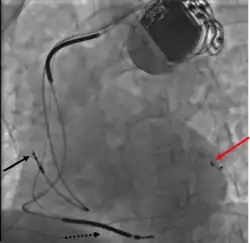

Three leads can be seen in this example of a cardiac resynchronization device: a right atrial lead (solid black arrow), a right ventricular lead (dashed black arrow), and a coronary sinus lead (red arrow). The coronary sinus lead wraps around the outside of the left ventricle, enabling pacing of the left ventricle. Note that the right ventricular lead in this case has two thickened aspects that represent conduction coils and that the generator is larger than typical pacemaker generators, demonstrating that this device is both a pacemaker and a cardioverter-defibrillator, capable of delivering electrical shocks for dangerously fast abnormal ventricular rhythms.